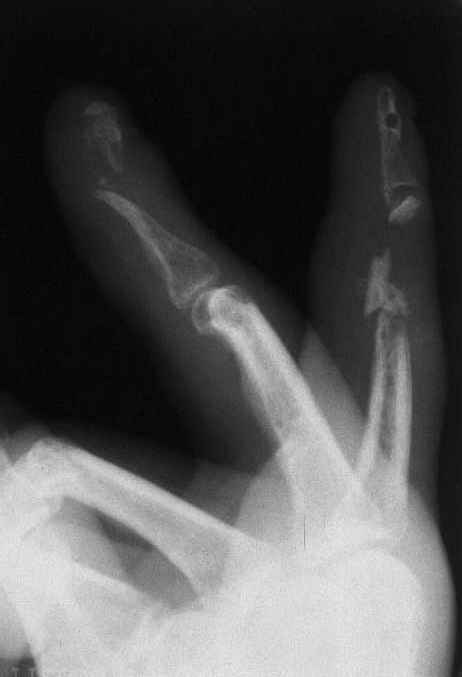

На представленных снимках пальцы правой кисти мужчины 42 года через 3 месяца после травмы циркулярной пилой.

Качательные движения в проксимальном м/ф суставе 3 пальца. Нарушены все виды захвата, в которых принимают участие 2 и 3 пальцы. Кожные покровы с большими рубцами по тыльной и боковой поверхности пальцев. Ни магистральный кровоток, ни микроциркуляция специальными методами не оценивались. Косвенно о трофических нарушениях свидетельствует распространенный остеопороз дистальных фаланг и очаговый остеопороз основных фаланг и головок пястных костей, причиной которого возможно является и длительная иммобилизация в аппарате внешней фиксации. Чувствительных нарушений нет.

Планируем: 3 палец - открытый артродез дистального м/ф сустава с минимальной фиксацией спицей, тенолиз и разработка проксимального сустава (по этому пальцу в общем тактика ясна). 2 палец - обсуждается два варианта тактики:

1. Остеотомия основной фаланги, с последующей дистракцией в аппарате и удлинением последней до дистального м/ф сустава. Далее снова остеотомия - или неартроз, или эндопротез проксимального сустава, тенолиз. (Недостаток - будет потеряно время для восстановления функции сухожилий)

2. Костная пластика средней фаланги, одновременно тенолиз, артродез дистального м/ф сустава, разработка захватов. (Недостаток - опасаемся возможного некроза трансплантата вследствие ангиотрофических нарушений)Буду признателен за высказанные на форуме мнения по поводу пациента.